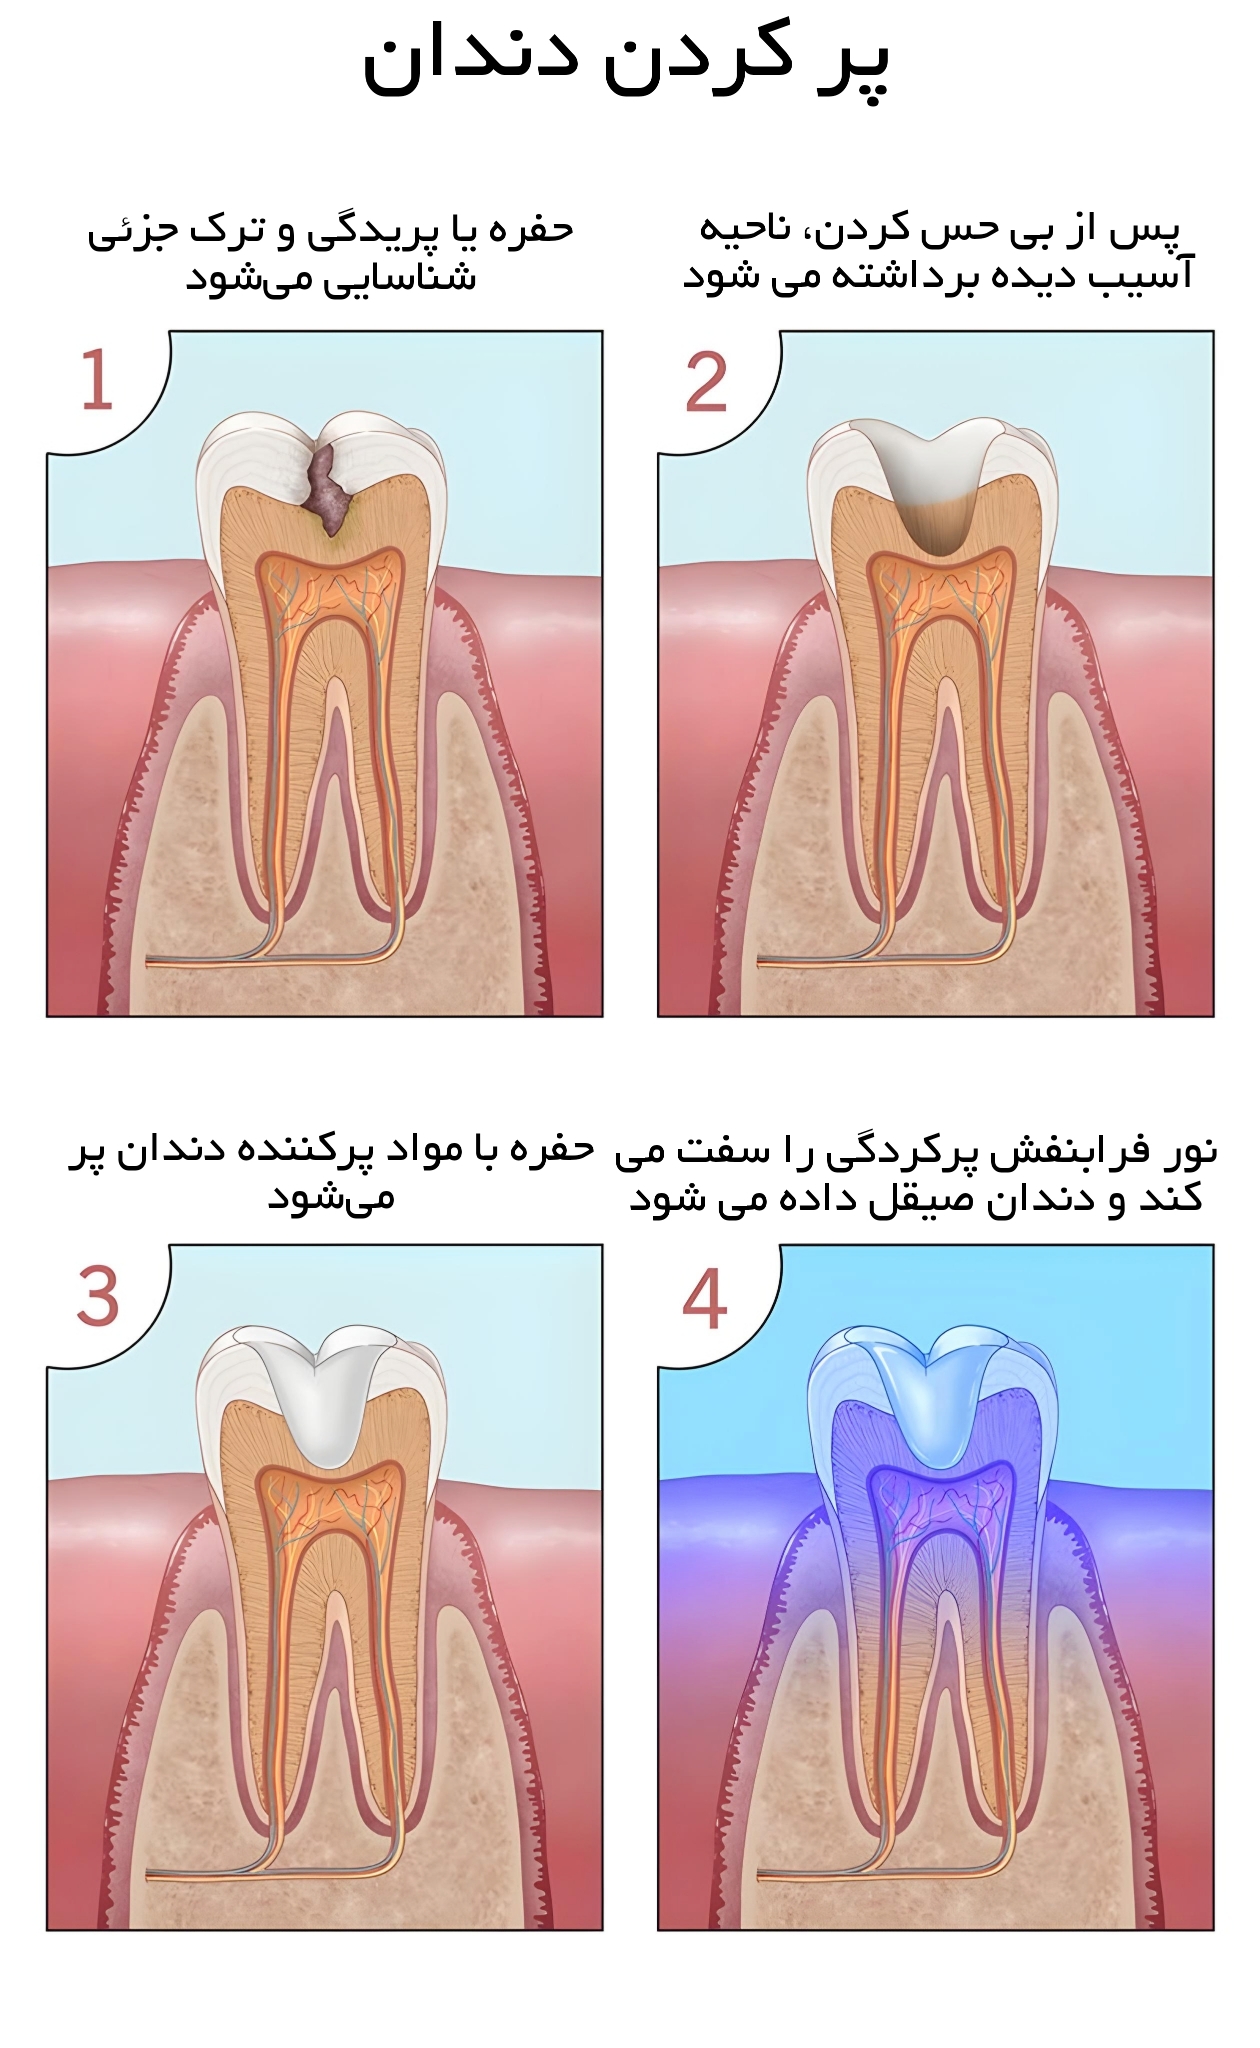

فرآیند و مراحل پر کردن دندان

دندانپزشک در ابتدا دندان و ناحیه اطراف را برای ترمیم قسمت آسیب دیده آماده و تراش میدهد. پوسیدگی یا آسیبدیدگی با لیزر یا هندپیس دندانپزشکی برداشته شده و جرمگیری این ناحیه برای پاک سازی از باکتریها یا ذرات باقیمانده پیش از تکمیل ترمیم انجام میشود.

برای پر کردن دندان با کامپوزیت ابتدا می بایست دندان پوسیده را ایزوله نمود. ایزوله کردن دندان پوسیده در ترمیم با کامپوزیت به این دلیل بسیار مهم است که اجازه نمیدهد رطوبت درمان باندینگ را با اختلال مواجه کند. دندانپزشک در باندینگ لایههای چسب و سپس ماده کامپوزیت را روی دندان میزند و آن را با تابش نور مخصوص خشک و سفت میکند. این نوع درمان زیبایی خاص خود را به همراه دارد.

1. متخصص دندانپزشک ابتدا دندان تحت درمان را ایزوله میکند تا بزاق به آن راه نداشته باشد و دندان خشک باقی بماند.

2. سپس با استفاده از دریل دندانپزشکی قسمت هایی که پوسیده و عفونی شده اند، برداشته می شوند.

3. رزین کامپوزیت به صورت لایه لایه در فضای خالی ایجاد شده قرار گرفته می شود تا دندان پر شود.

4. نور مخصوصی آبی رنگ به هر لایه از مواد پر شده تابانده می شود تا ماده کامپوزیت سفت شود.

5. پس از این که دندان کاملا پر شد، رزین کامپوزیت شکل دهی میشود تا سطوح و انحناهای آن کاملا مشابه دندان طبیعی شود.